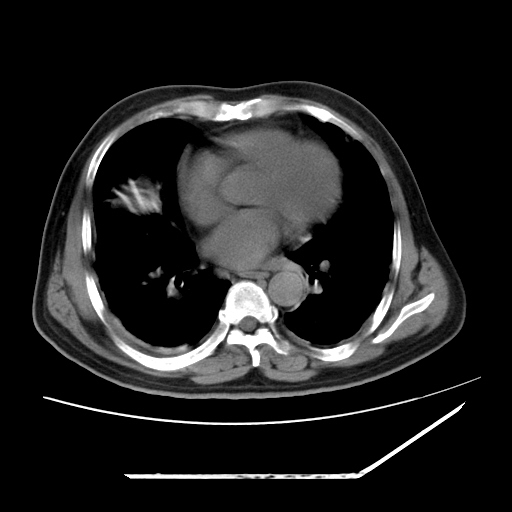

男,57,畏寒,发热

两肺野多发大小不一高密度灶,纵膈内见肿大淋巴结,要考虑转移瘤可能。双侧胸腔少量积液。

双肺多发结节样病灶,部分内见透光区,纵隔内见淋巴结肿大。结核临床如有畏寒,高热,白细胞增高首先考虑迁徙性肺脓肿(多是金黄色葡萄球菌感染)。

注意除外转移瘤。

1)考虑两肺感染性病变(金黄色葡萄球菌肺炎?);建议抗炎治疗后复查排除其他。2)双侧少量胸腔积液。